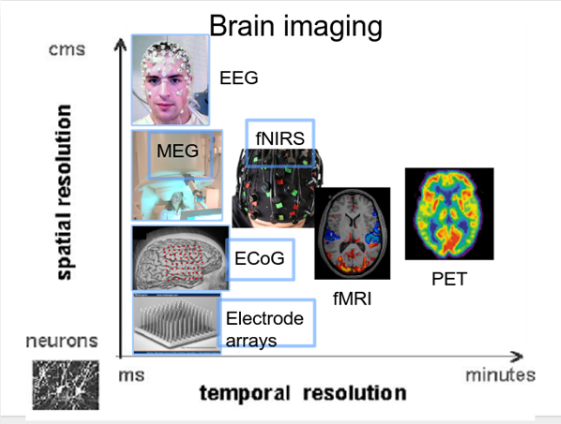

在下面的图像中可以看到不同的脑成像技术,在空间和时间分辨率上的比较:

比较

脑机接口可以使用任何类型的脑成像。这些包括功能磁共振成像、PET和近红外光谱(NIRS),它们依赖于血流的变化,以及分别测量大脑磁活动和电活动的脑磁图(MEG)和脑电图(EEG)。fMRI和NIRS的空间分辨率较高,但时间分辨率较差;MEG和PET具有较高的时空分辨率;脑电具有较低的空间分辨率和较高的时间分辨率。目前,fMRI和MEG依赖昂贵而笨重的设备;PET需要向血液中注入放射性物质。因此,依赖近红外光谱(NIRS)的方法,特别是依赖脑电图(EEG)的方法是最常用的。